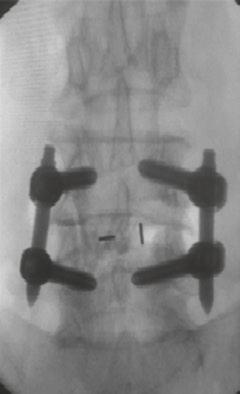

在过去的十年中,TLIF(经椎间孔腰椎椎体间融合)已经成为实现节段性椎体间融合的流行技术。最小通路技术的最新进展有助于通过微创方法进行手术,并提供充分的减压和固体融合。微创技术也有助于避免传统的后路开放入路[1,2]的许多缺点。Schwender等人[3]的一项研究报告了在接受微创TLIF手术的患者的视觉模拟评分和奥斯威特残疾指数评分有临床显著改善,100%的融合率为100%。在MIS病例中,通过更小更窄的解剖进行可视化。退行性脊柱侧弯存在复杂的脊柱病理,如脊柱旋转、透视镜解剖不良、椎弓根不对称和形状异常的椎弓根,可对MIS-TLIF构成严重挑战,导致椎弓根螺钉和钛笼[4]放置不正确。脊柱手术中的图像引导导航对MIS外科医生是一个宝贵的帮助,因为它允许更大的区域。透视可以帮助螺钉放置;然而,它增加了手术时间和辐射暴露给外科医生和手术室人员。据报道,徒手和透视引导下椎弓根螺钉置入时,腰椎移位率高达30%,胸椎移位率高达50%。mal定位的螺钉可能对脊髓、神经根和大血管造成潜在的损伤,也会降低脱位的稳定性。医学法律上对患者安全的担忧进一步加强了图像引导螺钉放置的必要性,以提高[5]的准确性。

计算机辅助脊柱手术(CASS)是一门使用新的基于计算机的技术的学科,包括立体定向、导航手术和机器人技术。导航辅助脊柱手术是一组技术,它允许外科医生在手术中获取与手术器械相关的实时、三维和虚拟的脊柱图像。